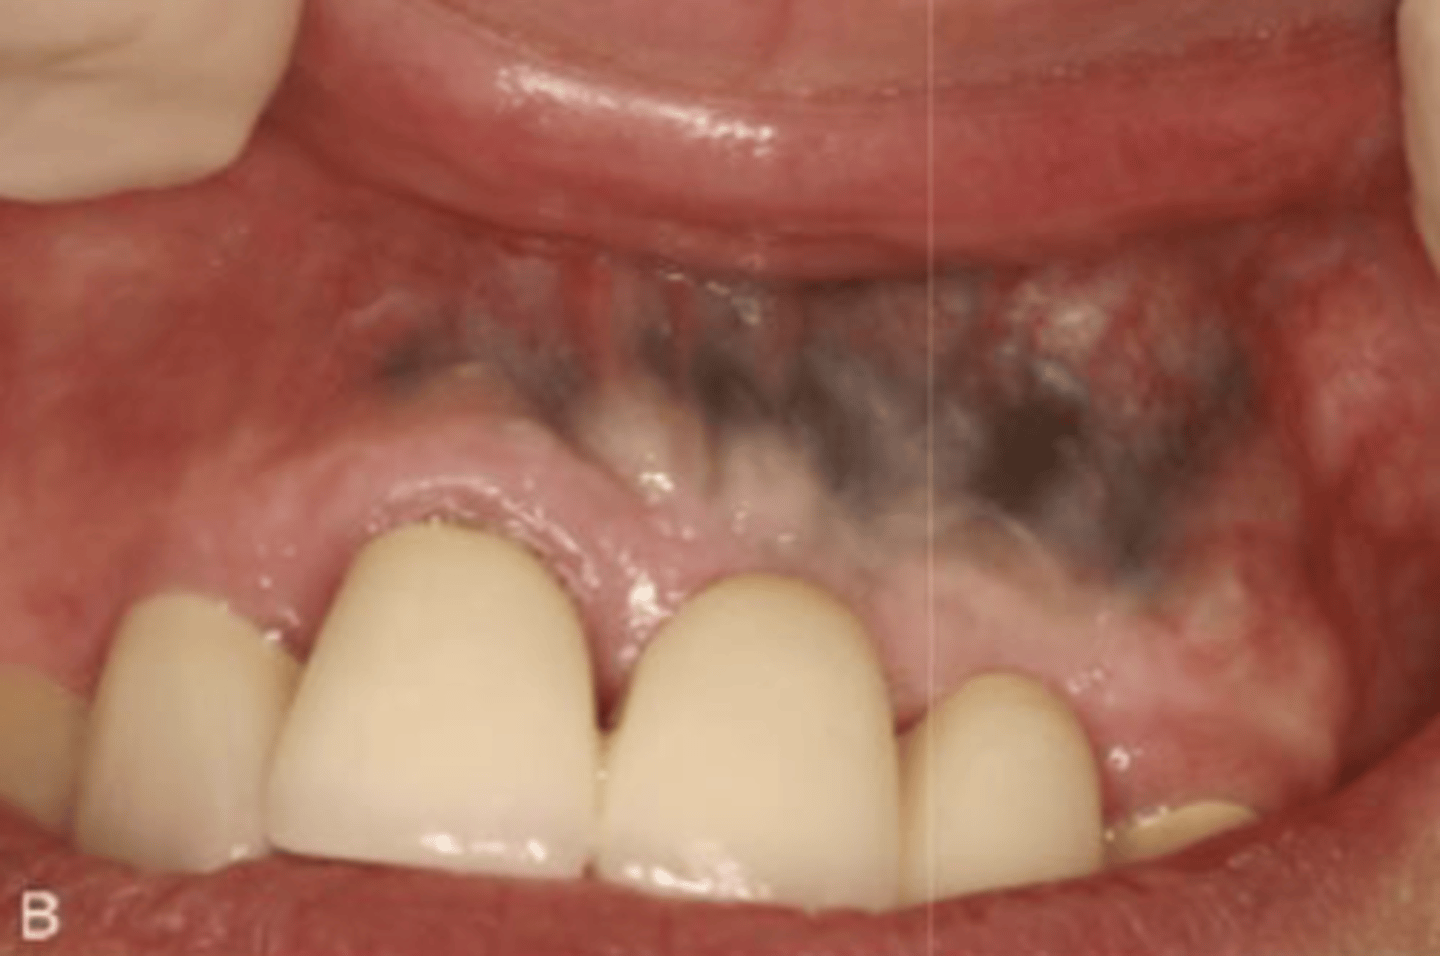

What type of pigmented lesion?

amalgam tattoo

These are clinical features of what?

- Asymptomatic, localized

- Blue-gray macule

- Localized around areas with amalgam restorations

amalgam tattoos

What is the most common location of amalgam tattoos?

gingiva/alveolar ridge mucosa (50%, then buccal mucosa, then floor of mouth)